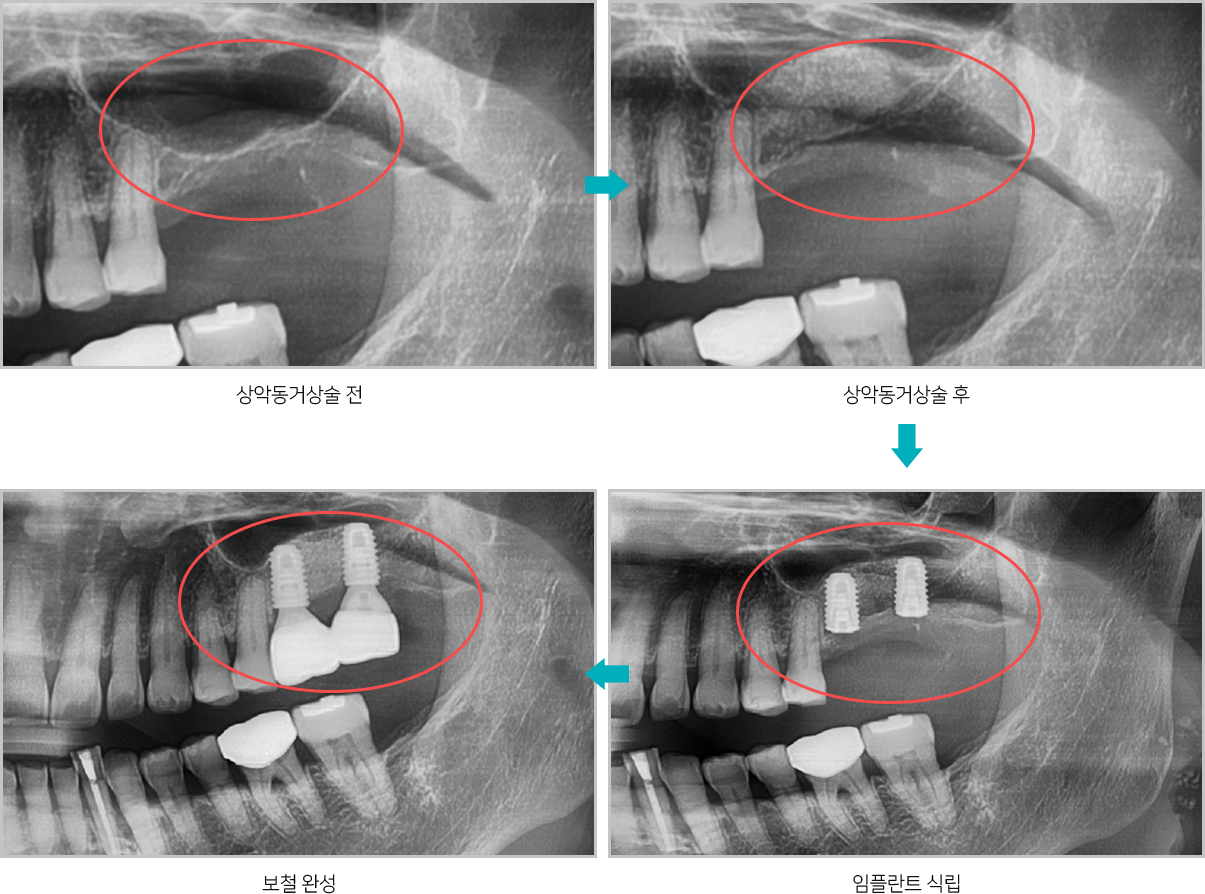

위턱뼈 속의 비어있는 공간을 상악동이라고 하는데

상악동과 잇몸뼈 사이에 임플란트를

심을 수 있는 만큼의

뼈가 남지 않았을 때, 잇몸뼈 위쪽에 위치한 상악동의

아래벽을 위쪽으로

들어올리고 그 공간에 뼈를 채워

넣어서 임플란트를 심을 수 있는 뼈의 양을

확보하는 술식입니다.

상악동거상술 전후

상악동거상술 모식도